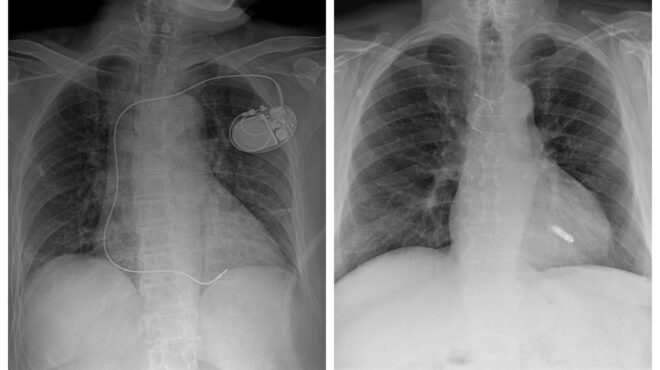

Τι πρέπει να γνωρίζετε για τις ανακλήσεις καρδιακών συσκευών